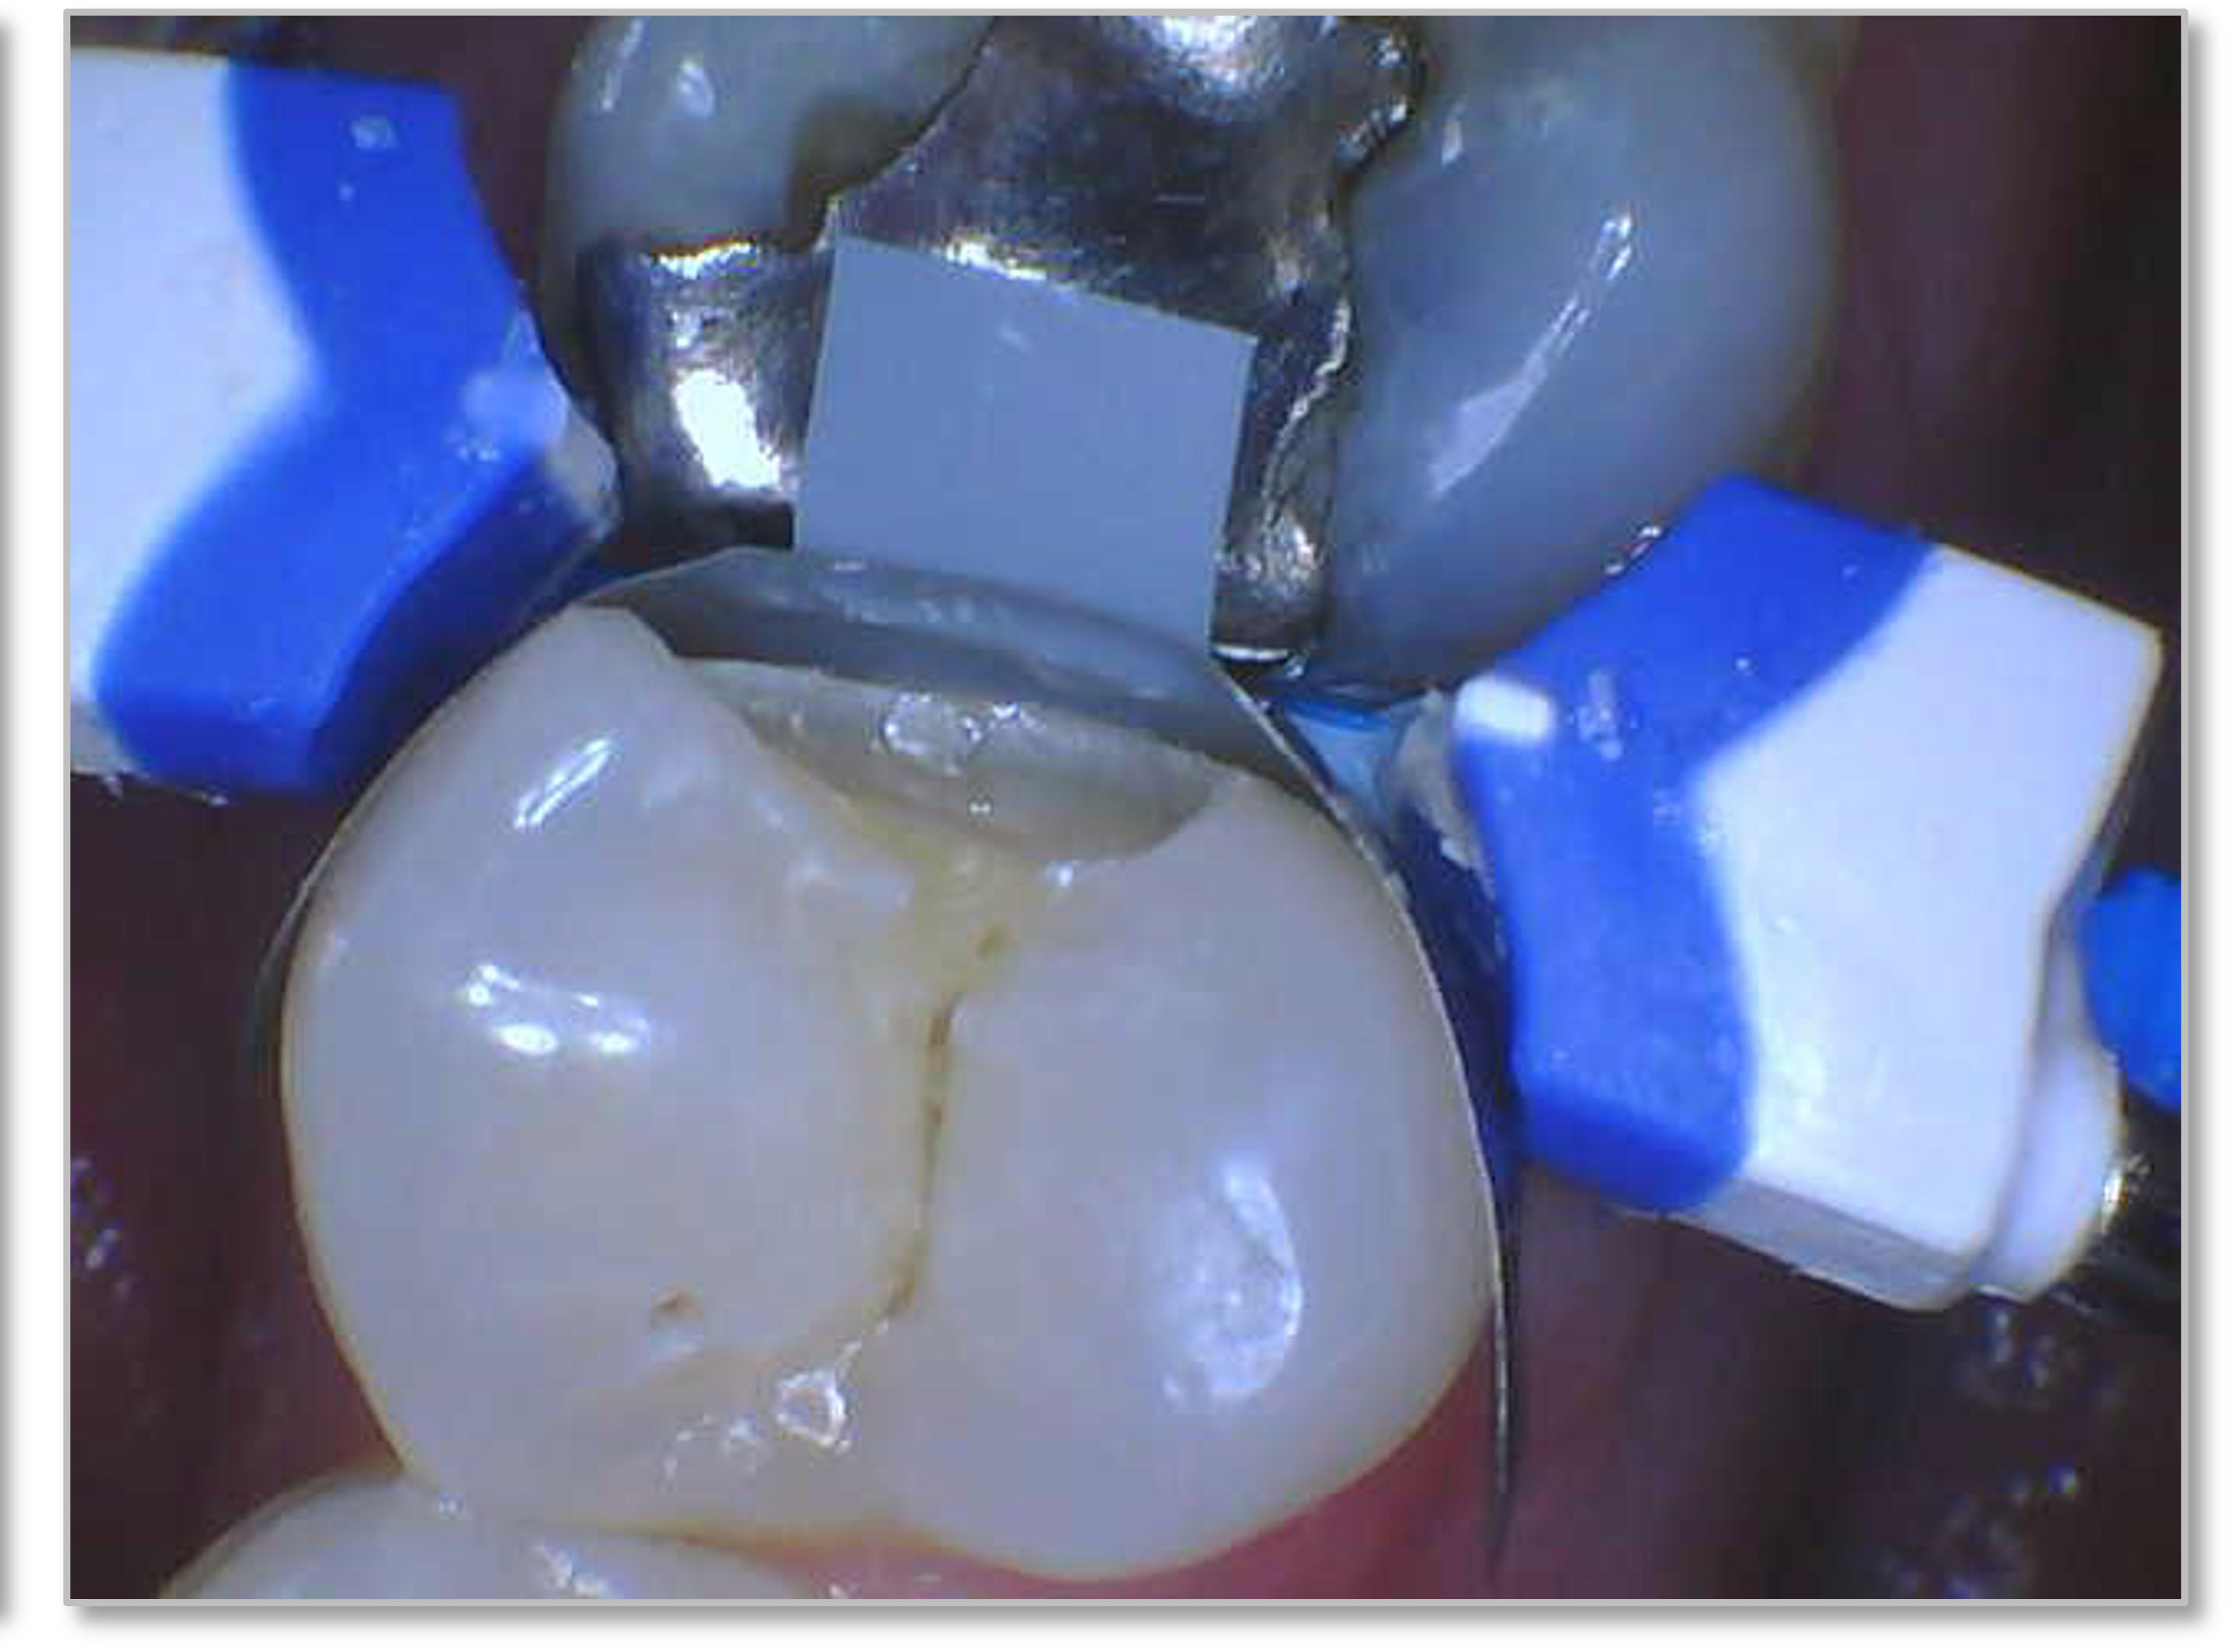

Figure 6a through Figure 6d show a procedure using a bulk fill packable as an interproximal Class 2, without using a bulk fill flow and not done with the snowplow technique to see how well the composite adapted to the margin. A light curable resin-modified calcium silicate liner (Bisco TheraCal LC) was used to perform an indirect pulp cap. A packable bulk fill composite was applied as a single increment layer to successfully restore the tooth. The material (Kerr SimpliShade Bulk Fill Packable) provided good adaptation to the tooth without gaps or polymerization stress lines and demonstrated great polishability and blendability. The patient reported no post operative sensitivity or discomfort in the 9 months after the restoration was performed. Sensitivity can be a concern if a composite is subjected to too much polymerization shrinkage.

Fig 6a. A procedure using a bulk fill packable as an interproximal Class 2, without using a bulk fill flow and not done with the

snowplow technique. A light curable resin-modified calcium silicate liner (Bisco TheraCal LC) was used to perform an indirect pulp cap. A

packable bulk fill composite was applied as a single increment layer. The material (Kerr SimpliShade Bulk Fill Packable) was used to provide

good adaptation to the tooth without gaps or polymerization stress lines and demonstrated great polishability and blendability.

Fig 6a. through 6d. A procedure using a bulk fill packable as an interproximal Class 2, without using a bulk fill flow and not done with the